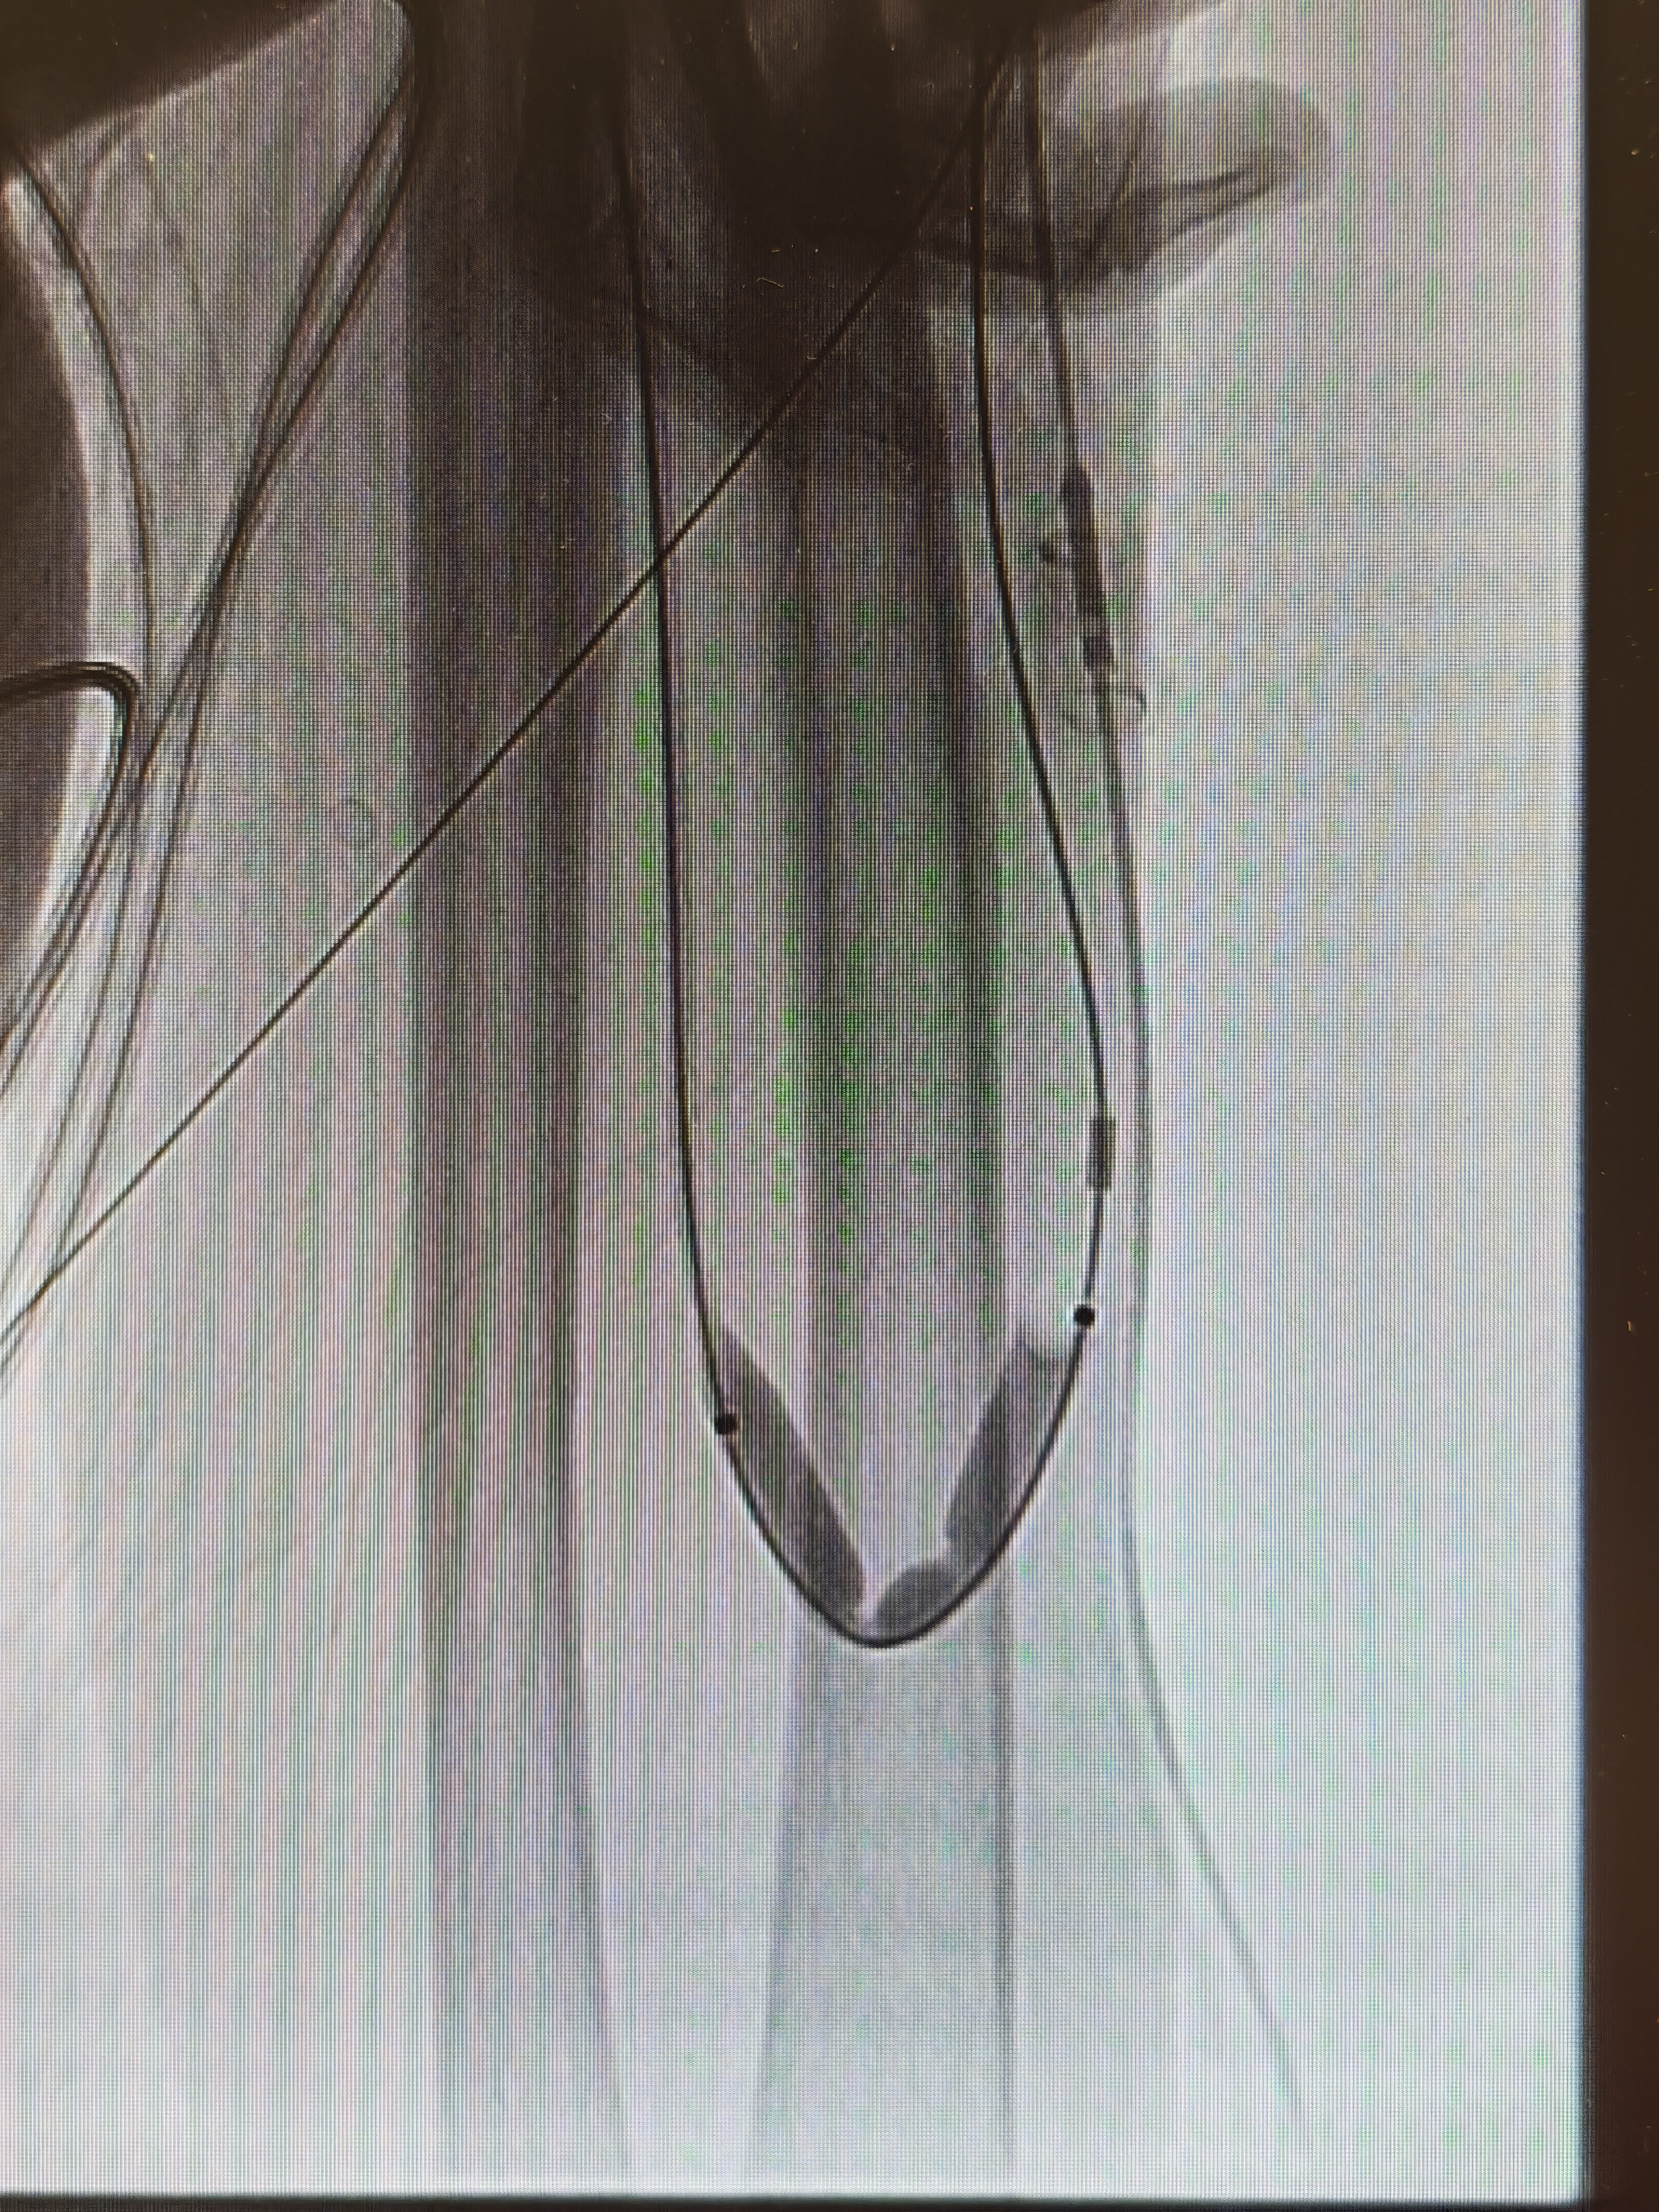

患者入院后,医院立即启动肾病血透通路 MDT 多学科会诊。四川泰康医院副院长、血管介入博士、血管通路专家郭伟昌牵头,为患者量身制定个体化手术方案。在充分术前准备下,郭伟昌副院长带领肾内科团队,为患者实施经肱动脉入路 DSA 下动静脉内瘘造影 + 球囊扩张 + 腔内溶栓术。术中造影显示,患者内瘘瘘口狭窄约 80% 并伴血栓形成。郭伟昌副院长精准操作,以 5 mm 高压球囊扩张病变,并予以尿激酶溶栓。术后复查造影显示,狭窄段完全开通,血流通畅。术后第二天,患者即可使用内瘘顺利透析,彩超复查血流量恢复至理想水平。